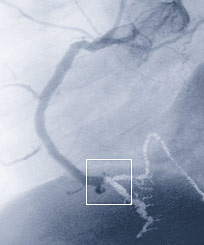

Herzklappenzentrum

Zudem arbeiten unsere Spezialisten für kardiale Diagnostik und Bildgebung, Herzchirurgen, interventionelle Kardiologen der Zentren sowie die Herzanästhesisten der Klinik interdisziplinär im Bereich der Diagnostik und Behandlung von valvulären Herzerkrankungen (Herzklappeneingriffen) zusammen.